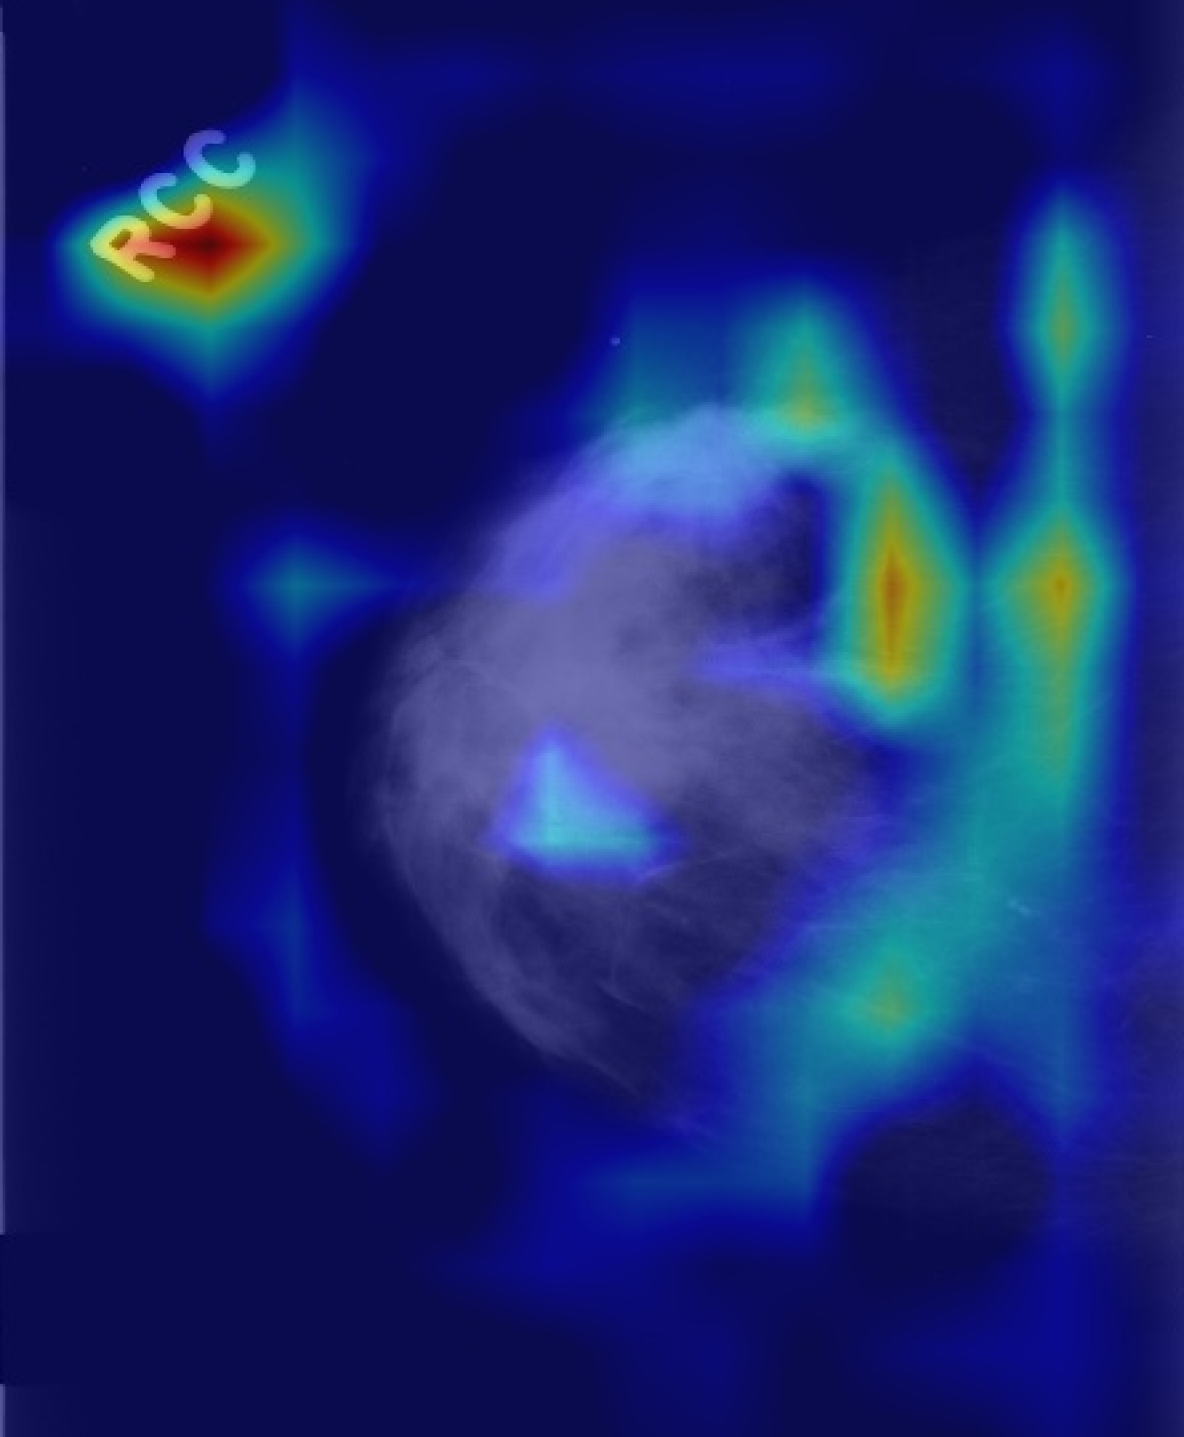

Figure 3: Result attribution heatmaps for mammography [17] and chest X-ray [14]: (a) original image overlayed with annotation contours (and arrows for missing GT), (b) our attribution framework. (c) GradCAM [25] (d) Saliency [26].

Attribution: We compared our attribution network against the gradient explanation saliency map [26] (SAL), and the network/gradient-derived GradCAM [25] visualizations. We limited our comparisons to these direct approaches, as they are widely used within medical imaging [13], and inherently valid [2]. Popular reference based approaches either utilize blurring, noise or some other heuristic [9, 8, 31], or were not available [7], therefore could not be considered. Quantitatively, we relate (i) the result-maps M^^𝑀\hat{M} to both organ, and ground truth (GT) annotations, and (ii) to each other. Particularly for (i) we studied the Hausdorff distances H𝐻H between GT and M^^𝑀\hat{M} indicating location proximity. Lower values demonstrate better localization in respect to the pathology. Further, we performed a weak localization experiment [8, 9]: per image, we derived bounding boxes (BB) for each connected component of GT and M^^𝑀\hat{M} attributions. A GT BB counts as found, if any M^^𝑀\hat{M} BB has an IOU 0.125absent0.125\leq 0.125. We chose this threshold, as a proficient classifier presumably focuses on the masses’ boundaries and neighborhoods, thereby limiting possible BB-overlap. We report average localization L𝐿L. For (ii) we derived the area ratio A𝐴A between M^^𝑀\hat{M} and organ-mask (breast-area) or whole image (chest X-ray). Again, lower values indicate a smaller thereby clearer map. Due to missing GT we could only derive (ii) for TBC. All measurements were performed on binary masks, hence GradCAM and SAL had to be thresholded. We chose the 50,75,9050759050,75,90 percentiles, i.e. compared 50,25,1050251050,25,10 percent of the map-points. Where multiple pathologies, or mapping results occurred we used the median for a robust estimation per image. Statistically significant difference between all resulting findings was formalized using Wilcoxon signed-rank tests, for α<0.05𝛼0.05\alpha<0.05. Additionally we followed [2], and tested our network with randomised parametrization (labels have no effect in our case).

As seen in Table 1, our framework achieves significantly lower H𝐻H, than either GradCAM or SAL at all threshold levels. Moreover, we report significantly better weak localization (L𝐿L) which underlines the higher accuracy of our approach. Qualitatively our attribution-maps are tighter focused (c.f. Fig. 3(b)) and enclose the masses. The former is also expressed by the lower overlap values A𝐴A. All p-values where significantly below 1e-21e-21\text{e-}2, hardening our results. Randomization of the ANN’s weights yields pure noise maps, hence we pass [2]’s checks.